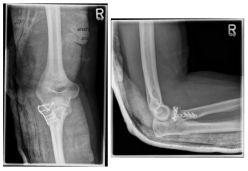

Photo: The fracture on the left is after an operation with a plate and screws |